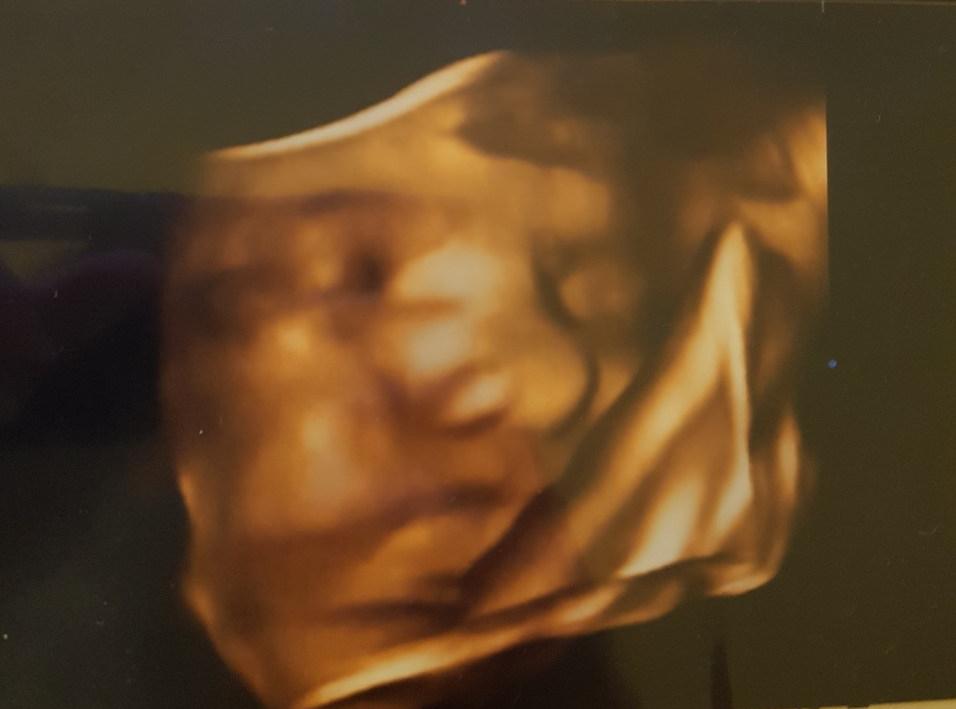

Két csokit is ettem, hogy éber legyen a baba, és rendesen mozogjon majd ultrahang közben, de mivel félórás csúszásban voltak előttem, mire sorra kerültem, sajnos a kicsi magzatom már elaludt. Az első 4D-s fotó nem is sikerült jól, mert a kis kezecskéivel el is takarta a szemét, de a vizsgálat végére azért sikerült egy picit megmozdítani.

Mindent rendben találtak a vizsgálton, arányos szép formás babának titulálta a vizsgáló a magzatomat. Érdekes, hogy az ember azt hinné, minél idősebb a baba, annál izgalmasabb az ultrahang, de valójában nem, mert már nem fér rá a képernyőre, nem látod egyben, mindig csak egyik testrésze látszik, és vagy látszik vagy nem a méhlepénytől és a többi cucctól. Azért az aranyos, amikor hirtelen látsz egy kis talpat az apró lábujjakkal.

A 4D-s felvétel egyébként igazán feldobja az ultrahangozást, mert valóban kis emberke formát ölt, amit látunk, és persze a rokonok is megőrülnek érte, és már rögtön kezdik találgatni, hogy kire hasonlít a gyermek. Nagyon kíváncsi vagyok, hogy mennyire fog hasonlítani ez a kép a kisfiamra, amikor a kezembe foghatom végre.